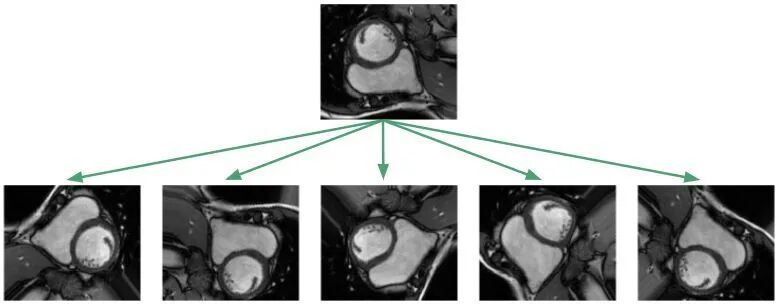

与其他数据不足的场景相同,医学图像也可以借助数据扩张实现网络的训练。比如下图所示,通过随机旋转、平移、缩放、裁剪、弹性形变等手段,对原始图像进行变换: